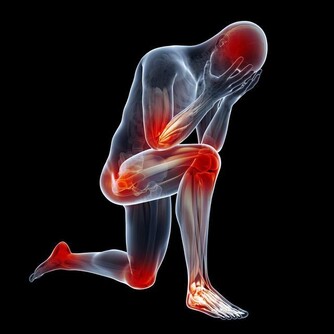

二、心梗

心梗被稱為“迅捷的殺手”,患者常常在很短時間內,就被奪去了生命。

其實,雖然心梗從發作到猝死只有短短幾分鐘,但很多患者在心梗發病前,是有一些預警症狀的,

這些症狀往往會持續一兩天,如果在這時候儘早干預,就能有很大概率挽救生命。

心梗前兆如下:

1、長期高血壓、冠心病的老年人,無緣無故拉肚子,吃藥也不見好轉。

很多心梗,會表現為腹部不舒服。

2、在勞累或運動後,出現肩膀疼痛、後背疼痛、牙齒疼痛、喉嚨發緊等症狀,

且這些症狀會隨著運動的增多而加劇。

3、心絞痛、胸悶氣短等症狀在近期加劇。

例如原本走1公里才胸悶氣喘,現在走500米就不行了,那要趕快去醫院檢查。

4、突然出現心慌和嚴重憋氣的情況,吃藥也不管用。

5、突然出現嚴重胸痛,並伴有大汗淋漓的情況。